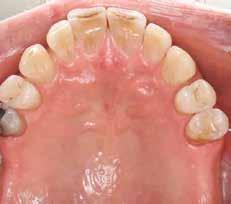

1. ábra: A műtét előtti szituáció, megfigyelhető az implantátumok közötti konkáv terület, ahova könnyen beragad az ételmaradék, és könnyen kialakul a periimplantitis.

Egy 47 éves páciens jelentkezett nálunk egy alsó, hátsó foghiánnyal, ahol jelentős csontfelszívódást tapasztaltunk a moláris fogak korábbi eltávolítása miatt (1. ábra). Két implantátum körül is volt ínyrecesszió, illetve a keratinizált íny mennyisége minimális volt (kevesebb, mint 1 mm). 4 hónappal az implantációt követően ínykorrekciót végeztünk.

A páciens mobilis implantátum körüli lágyszövettel rendelkezett, a keratinizált íny szélessége kevesebb volt, mint 1 mm és a nyálkahártya vastagsága nem érte el a 2 mm-t. Az ínyszél az implantátum platform vonalában volt. Az alábbi műtéti technikával jelentős javulást sikerült elérnünk az implantátum körüli lágyszövetek minőségében és a nem elmozduló keratinizált szövet szélesedett 4 mm-rel. A Kígyótechnikánál alkalmazott elforgatott lebeny a szabad keratinizált íny lebeny előnyeivel növeli a nem elmozduló nyálkahártya szélességét az implantátum körül. Biztosítja továbbá a jó vérellátást és a nyeles lebeny stabilitását, ami kisebb mértékű zsugorodást eredményez, mint egy szabad lágyszövet lebenyátültetésnél (29).